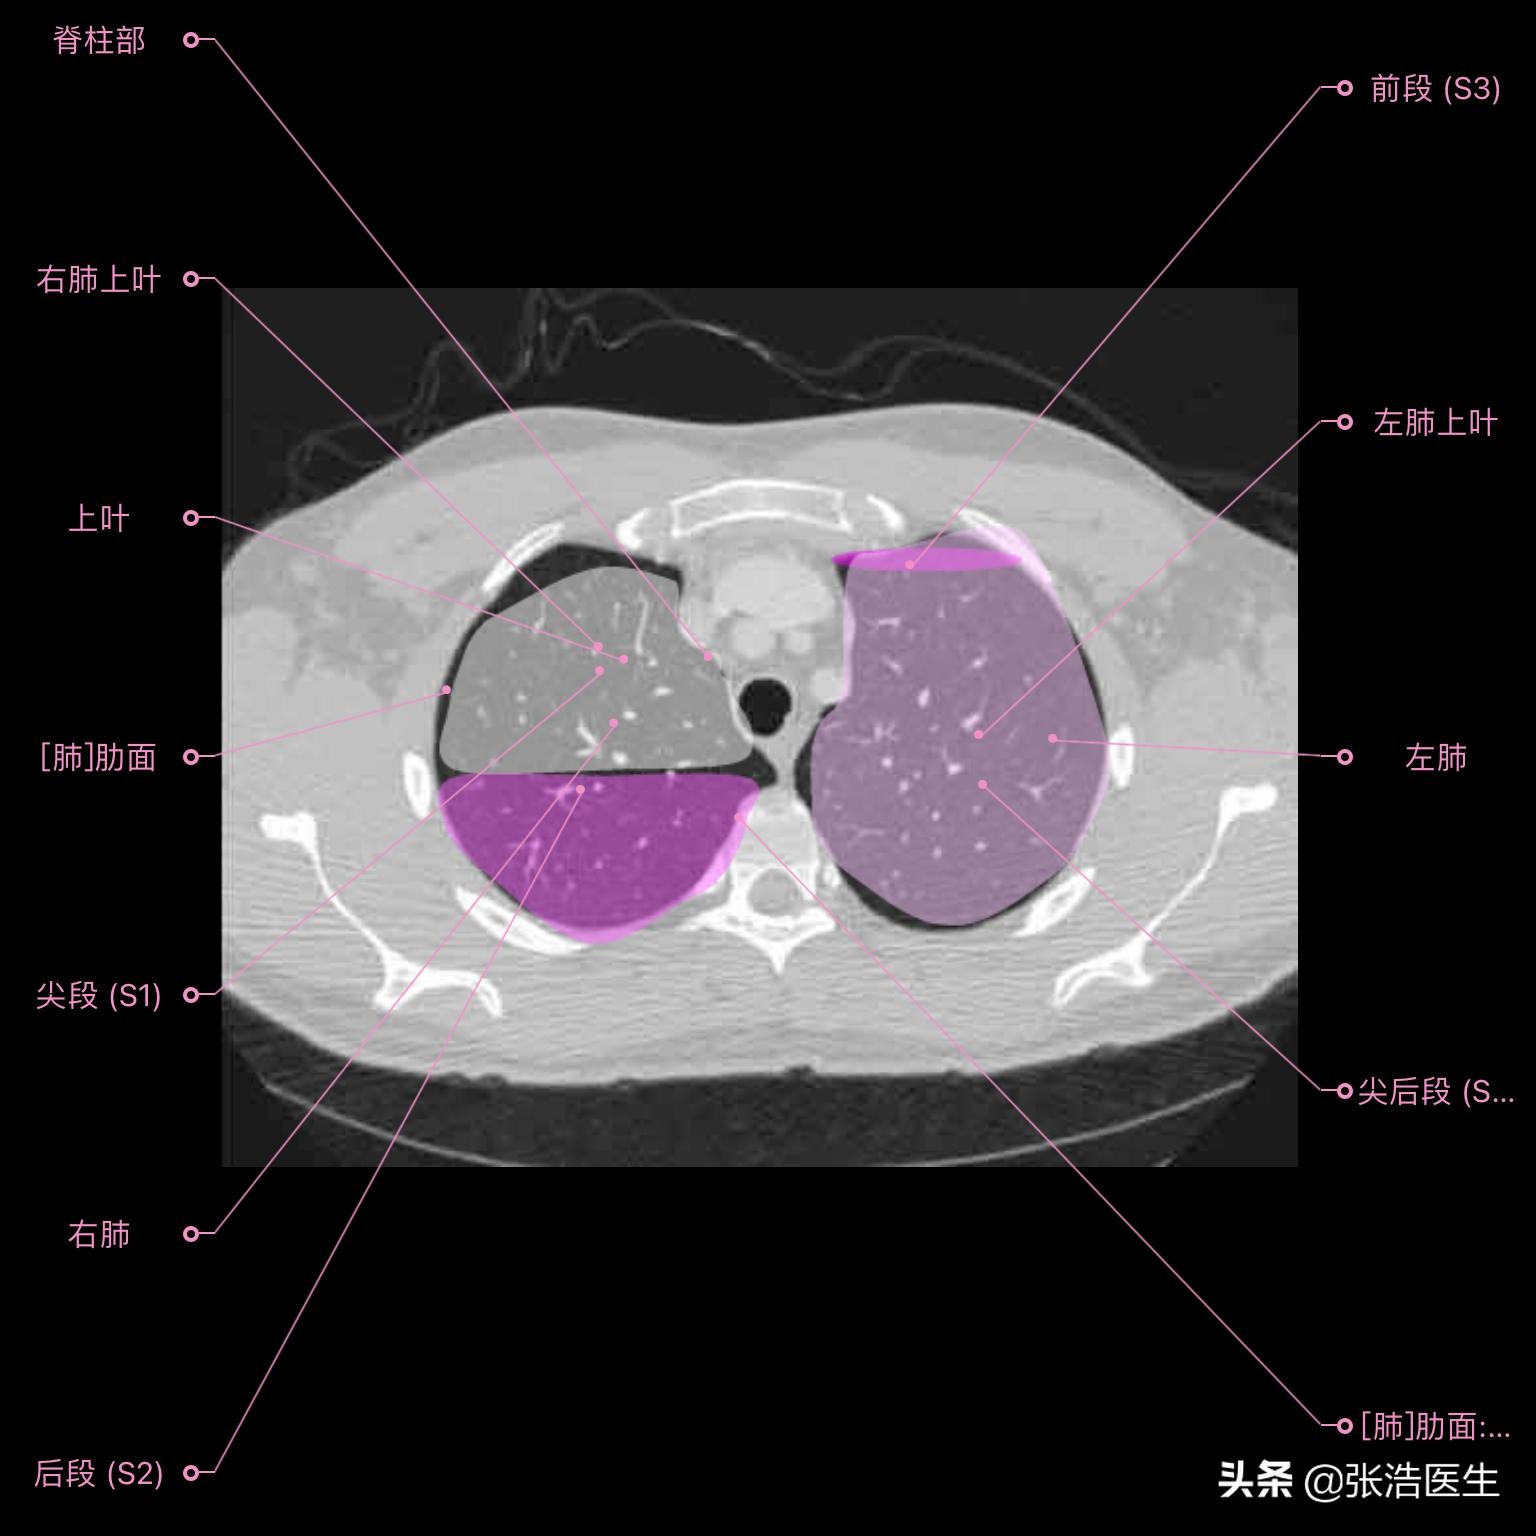

肺部CT横断面高清解剖图谱(图层2)